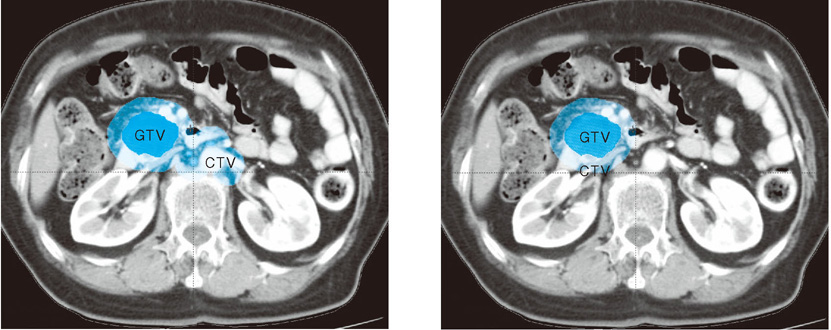

まずCTVとは画像診断で明らかに腫瘍が存在すると考えられる肉眼的腫瘍体積(gross tumor volume:GTV)にその周囲への顕微鏡的進展と,顕微鏡的転移を疑うリンパ節を含んだ体積のことを指す。すなわち本設問はCTVが単にGTVに局所の顕微鏡的進展のみを加えるだけで,腫大のないリンパ節への照射を省略できるか否か,またできるとすればどの範囲か,と言い換えることができる(図6)。

図6 臨床標的体積設定法の例

肉眼的腫瘍体積(gross tumor volume : GTV) はCT上原発巣と腫大したリンパ節と定義される(濃青色)。

また臨床標的体積(clinical target volume : CTV(薄青色))はGTVに顕微鏡的に腫瘍が進展していると考えられる範囲を付加した体積と定義される。

CTVに腫大のない(所属)リンパ節領域を予防的に含んだ場合(左)と含まない場合(右)の例を示す。

CTVの大きさが大きく異なることがわかる。